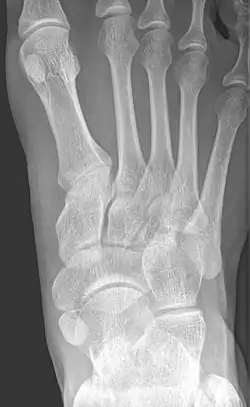

![]() X-ray of the foot showing an accessory navicular bone | |

From left to right: Type 1, 2 and 3